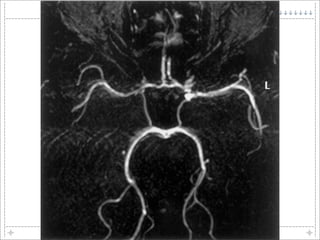

This document discusses blood-brain barrier (BBB) permeability and regulation. It describes the cellular components that make up the BBB, including endothelial cells, astrocytes, pericytes, and the mechanisms that control permeability, such as tight junctions between endothelial cells. It also discusses how BBB permeability is altered in various pathological conditions like stroke, trauma, infection, and neurodegenerative diseases.